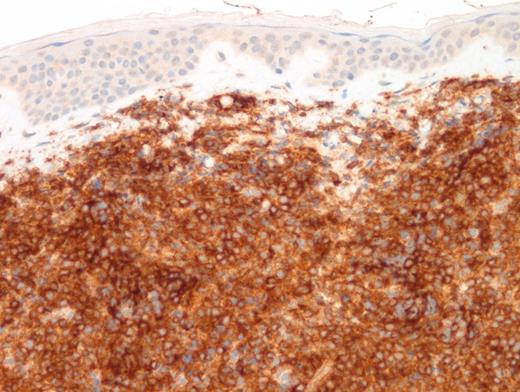

A 15-year-old girl presented with a three-month history of an erythematous rash on the medial side of the left breast. This was initially diagnosed as extramedullary myeloid tumor (EMMT). The patient received standard therapy for acute myeloid leukemia. Although bone marrow and cerebrospinal fluid analysis at the end of therapy showed no evidence of disease, there was cutaneous relapse in three months. An excisional skin biopsy was performed and showed an extensive/malignant appearing infiltrate involving dermis and underlying soft tissue and sparing epidermis and adnexal structures. Images of low- and high-power hematoxylin and eosin (H&E; Figures 1 and 2) as well as CD4 (Figure 3) and CD123 (Figure 4) immunostains are shown. In addition to these markers, a panel of immunostains revealed the dermal infiltrate to be positive for TdT, CD33, CD43, CD45, TCL1, TCF4, and CD68 KP1 (faint, focal).

Differential diagnosis with EMMT is challenging,1 particularly in CD56-negative cases. In this case, the faint expression of CD68 (KP1) coupled with CD33 and CD43 expression was suggestive of EMMT. However, CD33 and CD43 positivity can be seen in both BPDCN and EMMT. Furthermore, CD4 is commonly expressed in myeloid sarcomas with monocytic differentiation, especially in NPM1-mutated cases. Diffuse positivity for CD123 in a CD4+/TdT+ malignant neoplasm should alert the pathologist for a diagnosis of BPDCN even in the absence of CD56. In this case, additional TCF4 and TCL1 were eventually performed and showed diffuse positivity. The former marker (TCF4) is a crucial marker expressed in blastic cells with differentiation towards PDCs and its positivity allows exclusion of myeloid lineage. Dual expression of TCF4 and CD123 was found to be sensitive and specific for BPDCN.2 The distinction is critical since pediatric BPDCN patients benefit from lymphoid-directed therapy. A novel CD-123 directed targeted therapy3 was also recently approved by the U.S. Food and Drug Administration for adults and pediatric patients with this disease.